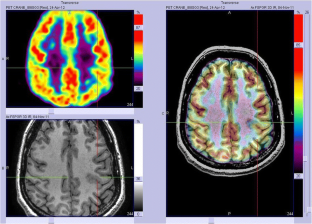

We analysed 18F-FDG PET scans from 103 consecutive patients (52 males, 7–65 years old) with histologically proven FCD2. PET and MRI data were first reviewed by visual analysis blinded to clinical information and FCD2 location. The additional value of electroclinical data and PET/MRI coregistration was assessed by comparison with pathological results and surgical outcomes.

Visual analysis of PET scans showed focal or regional hypometabolism corresponding to the FCD2 in 45 patients (44%), but the findings were doubtful or misleading in 37 patients and negative in 21. When considering electroclinical data, positive localization was obtained in 73 patients, and this increased to 85 (83%) after coregistration of PET and MRI data. Under the same conditions, MRI was positive in 61 patients (59%), doubtful in 15 and negative in 27. The additional value of PET was predominant in patients negative or doubtful on MRI, localizing the FCD2 in 35 patients (83%). Interobserver agreement correlated with the grade of hypometabolism: it was good in patients with mild to severe hypometabolism (82–95%), but moderate in those with subtle/doubtful hypometabolism (45%). The main factors influencing positive PET localization were the grade of hypometabolism and the size of the FCD2 (P < 0.0001). Misleading location (nine patients) was associated with a small FCD2 in the mesial frontal and central regions. Following limited cortical resection mainly located in extratemporal areas (mean follow-up 5.6 years), a seizure-free outcome was achieved in 94% of patients, including Engel’s class IA in 72%.

In this series, 18F-FDG PET contributed to the localization of FCD2 in 83% of patients. This high localizing value was obtained by integration of electroclinical data and PET/MRI coregistration. This approach may help improve the surgical outcome in extratemporal epilepsy, even in patients negative on MRI.